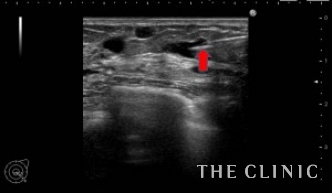

エコーで確認しながら、確実にヒアルロニダーゼ(ヒアルロン酸溶解剤)をしこり内に注入します。注入すると溶解剤とヒアルロン酸が反応して水のような液体になるため、すぐに吸引することができます。

こちらが吸引したヒアルロン酸です。

しこりが消失したことにとても満足されていました。